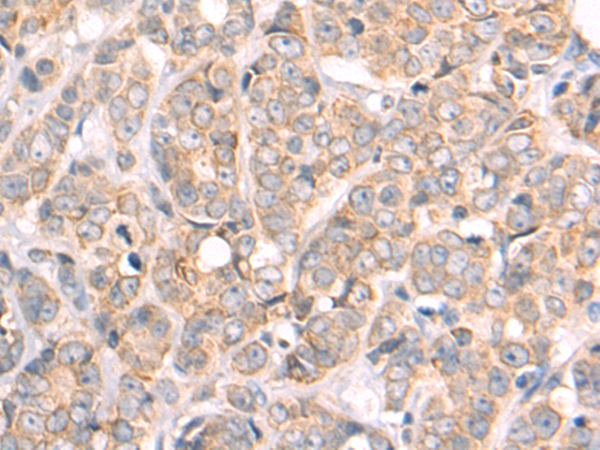

分类: 科研抗体货号: P09867别名: MAI; MAAI; MAAID; GSTZ1-1应用: WB,IHC反应种属: Human, Mouse, Rat